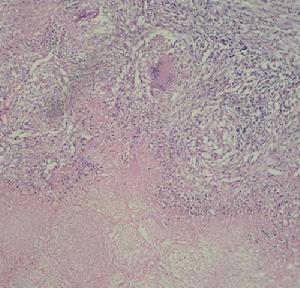

腦膜瀰漫充血,腦回普遍變平,尤以腦底部病變為最明顯,故雙有腦底腦膜炎之稱。延髓、橋腦、腳間池、視神經交叉及大腦外側裂等處的蛛網膜下腔內積存較多垢濃稠膠樣滲出物,呈灰白色乃至灰綠色混濁狀態。濃稠滲出物及水腫包圍擠壓顱神經可引起顱神經損害。炎症可波及腦幹脊髓及神經根。腦部血管周圍有漿細胞及淋巴細胞浸潤,早期主要表現為急性動脈炎。病程越長則腦血管增殖性病變越明顯,可見閉塞性動脈內膜炎。以致腦梗塞軟化或出血。

(2)該病常為全身性血行播散性結核的一部分,發病原因主要是因為患兒免疫力低下。原髮結核病病時,病灶內的結核桿菌可經血行而停留在腦膜、腦實質、脊髓內,形成隱匿的結核病灶,包括結核節結、結核瘤。當上述病灶一旦破潰,就會經血行播散至腦脊髓內形成結核結節,這些結節破潰後有大量結核菌進入蛛網膜下腔,引起腦膜、腦實質、脊髓的充血、水腫,腦血管炎等病理改變。半數以上患兒伴有粟粒性肺結核。當患者的免疫功能降低或因年老,病灶內的結核菌激活而破入蛛網膜下腔,隨腦脊液播散,歷時數天至數周即可引起結核性腦膜炎。炎性反應可迅速增加,但其程度和菌壁的抗原物質引起的超敏反應有一定的關係。炎性過程產生的大量滲出物多沉積在腦底池,隨時間的進展可引起蛛網膜炎,此時成纖維細胞進入滲出物,腦膜漸漸增殖變厚,當影響腦膜對腦脊液的吸收可引起交通性腦積水,若因粘連而阻塞第四腦室正中孔及側孔可引起梗阻性腦積水。